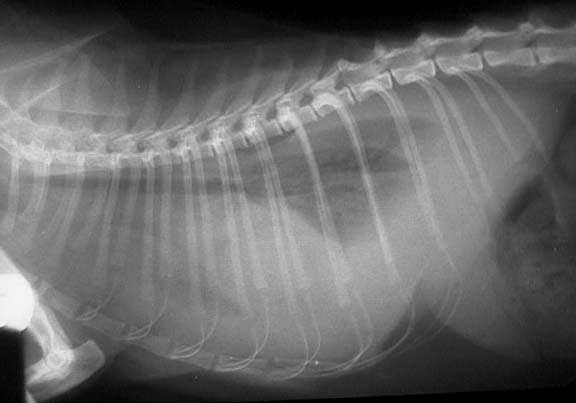

This view is towards the rear of the abdomen.

K- Kidneys (they are overlapping)

LI- Large intestine (filled with stool)

SI- Small Intestine

Sp- Spleen

B- Urinary Bladder (filled partly with urine)

The white arrow points to stainless steel sutures from a spay (OVH).